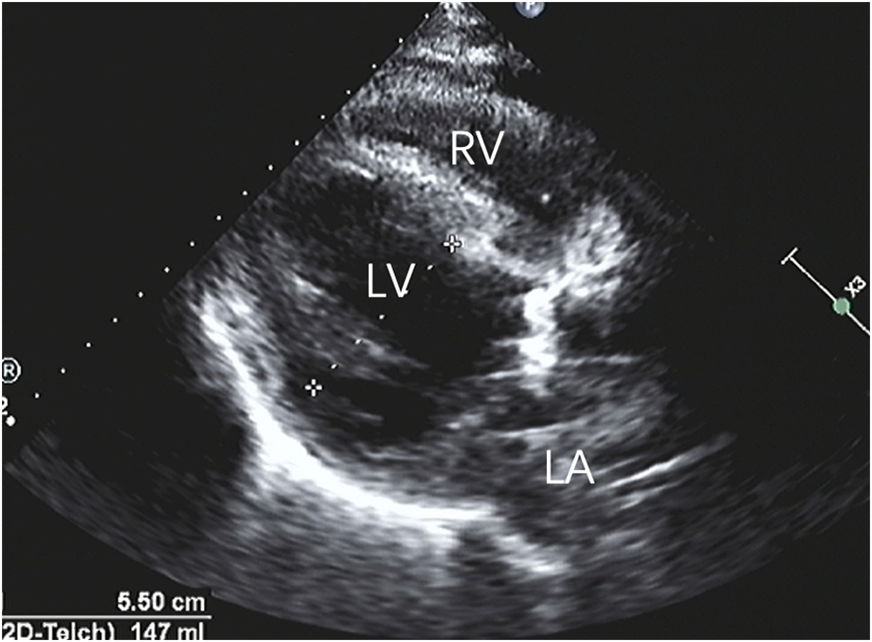

Postoperatively, the patient experienced a smooth recovery, with normal mechanical valve opening and closing sounds. CT scans revealed a satisfactory anastomosis of the aorta and coronary arteries, while transthoracic echocardiography (TTE) indicated a significant improvement in left ventricular ejection fraction and anterior wall motion (Figure 4). During a three-year follow-up, the patient's outcome remained favorable.

Figure 4

After repairing the rupture of the aortic sinus, the myocardial dissection resolved, and the anatomical structure returned to its normal state.